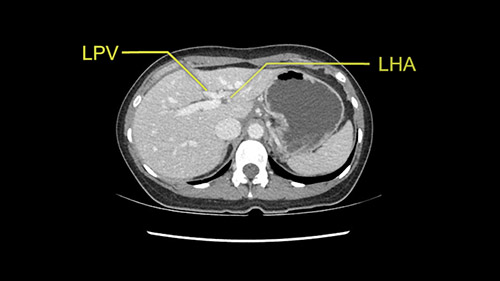

So the issue with regards to resection. A left sided tumor. I believe I can see the falciform ligament right here so we’re looking at a resection of Segments 2, 3 of the left lobe of the liver. The left portal vein is right there. I think we’ll be wiser to take the left portal vein and therefore get well into Segment 4 and do a left hemihepatectomy. Certainly, one does not need to take the middle hepatic vein; it’s miles from the tumor.

So I have to say that I would do this open, not laparoscopically because of the size of the tumor itself. Upper abdominal incision. Almost certainly, we’d be able to flip this very exophytic lesion up. Intraoperative ultrasound will show the relationship of the tumor and the left portal vein but the dissection at the base of the liver, as I look at things here, I can see the left hepatic artery which sneaks up to the left of the portal vein, should be out of harm’s way so I can take the Segment 2-3 left hepatic artery. The left portal vein is somewhat compressed. But by the time you pull the liver up a bit, you’ll be able to pull that left portal vein out to length and get a good margin on it.

My plan would be to leave the caudate lobe intact. You usually have to divide the caudate branches. I can see one of the caudate branches here coming off the left portal vein. You usually have to take that to get adequate length although you might be able to divide the portal vein past that left caudate branch.

Now let’s look at some specific anatomical points for planning this surgery. First thing you see when you see a left hemihepatectomy is that where is the left portal vein and the right portal vein branching? And what is the stump of the left portal vein available for you for ligation? In this particular case, you’ll find that there’s overhanging of the tumor but left portal vein pedicle is sufficiently available for us for ligation.

The second is the left hepatic artery. The tumor is displacing the arterial system. So one of the important points which we need to see intraoperatively is to identify and preserve the right artery very carefully and identify the left hepatic artery for ligation.

Once you identify the inflow of the left portal vein and the hepatic artery, its always a good idea to ensure that the bile duct is also carefully seen and preserved. The problem with the bile duct is it is thin and it might have a biliary variation which you are not appreciating on a CT scan. If there is a biliary variation, one has to be very careful not to injure the right ductal system and when you are resecting the left lobe of the liver. This is particularly true because you are having an overhanging tumor and that can distort the anatomy so one has to be careful and slow down when you are trying to ligate or identify the biliary system. It’s a good idea just to loop up the vessels, identify them and then ligate them only when you are certain that you are preserving the vasculature to the right side. I’ll prefer to ligate the inflow at this point of time. The left hepatic artery and the left portal vein to be ligated.

The other option of course is to do an anatomical left hepatectomy. In that case, I will start mobilizing of course the left lobe and try to find the ligamentum venosum, take it down and go around the left hepatic vein. I think, importantly in these cases and in this case, as you can see in the venous phase, that’s clearly a moment to stop. Because the left hepatic vein is pretty close to the middle hepatic vein as sometimes it is so you may need to dissect a little bit the parenchyma on top of the left hepatic vein to be able to go around the left hepatic vein safely.

Then I will turn my attention to the porta and I will dissect (and I usually go very high on the parenchyma) the left hepatic artery and likely the Segment 4 artery. Then I will take the left portal vein likely with a stapler. Very importantly, once you’re on the plane of transection, once you start transecting the liver, just on the right of the left hepatic vein, once you get to the plate and you’re far from the tumor it’s very important to change your plane of transection and quickly go to the left to avoid injuring the bile duct bifurcation or even the right hepatic ducts. I always transect straight down and once I’m getting close to the plate, I always make sure the plane gets transversely and really go into the left. That’s another key factor with a left hepatectomy. Otherwise, I think these are the key features from this case and there are two potential operations that could be done.